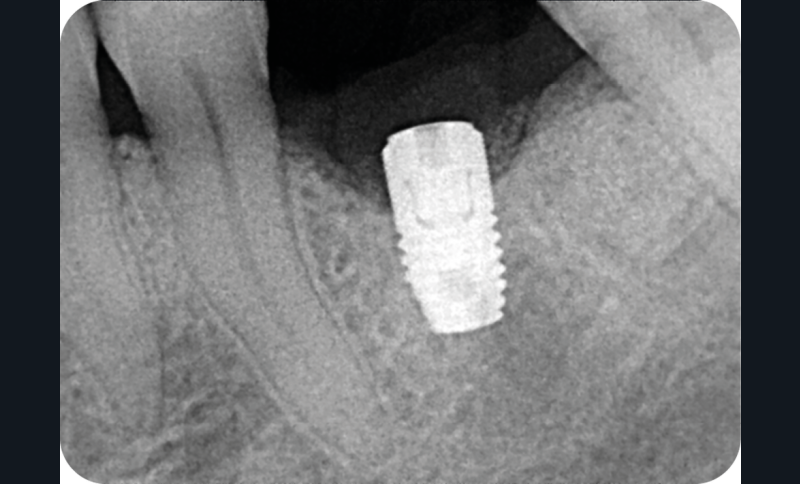

- Un implant posé en 2018 après la fin du traitement orthodontique

- Péri-implantite diagnostiquée en 2021

Chez ce patient, le traitement de la péri-implantite a comporté une chirurgie associant décontamination électrolytique de la surface implantaire, régénération osseuse guidée et enfouissement de l’implant. Le résultat à 2 ans est très moyen au vu du pourcentage de régénération osseuse obtenu. Comment peut-on prévoir un tel résultat alors que l’on a suivi les recommandations à la lettre, que l’on a utilisé les dernières technologies de décontamination, que l’on y a mis tous les moyens, que le patient est en bonne santé générale et qu’il vient en plus régulièrement aux séances de thérapeutique de soutien ? Le succès du traitement des péri-implantites n’est pas simple à obtenir, surtout quand un élément clé est compromis… la maintenance personnelle ! En effet le succès n’est possible que si le contrôle de plaque quotidien est optimal et, ici, ça n’était pas le cas. Le patient se brossait certes les dents, mais ne passait pas quotidiennement les brossettes, ce qui…